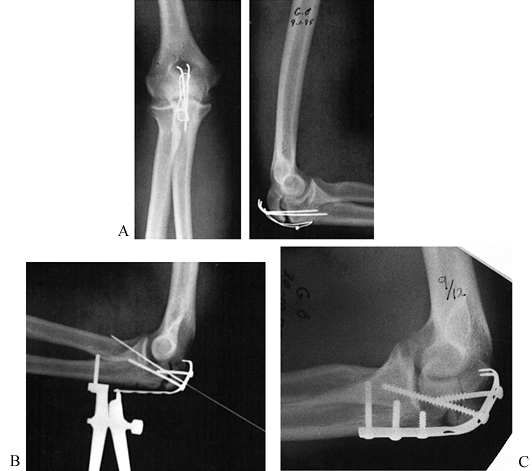

hook plate, as illustrated in Figure 27.12; or repeat tension band wiring, using a combination of screws and 18-gauge wire for the tension band.

![]() |

|

Figure 27.12. Nonunion of the olecranon. A: Inadequate tension band fixation of an olecranon fracture resulted in a nonunion. B:

Fixation has been removed, and a one third tubular plate has been fashioned as a hook plate, using the end hole as two sharp prongs. The tensioning device was applied after fixation of the plate to the olecranon fragment by a lag screw across the fracture site. Tensioning was then applied and supplemented by a long interfragmental fully threaded 3.5 mm screw. C: At 9 months, consolidation of the nonunion was occurring. This view also demonstrates the hook plate with its firm attachment into the olecranon. |

used (Fig. 27.13).

Figure 27.13. Nonunion of the olecranon. A: AP and lateral radiographs showing failure of a third tubular plate, resulting in nonunion. B:

AP and lateral radiographs. This fibrous nonunion was in an acceptable

position and, therefore, was treated with compression plate fixation

and an interfragmentary compression screw in situ, resulting in rapid healing.